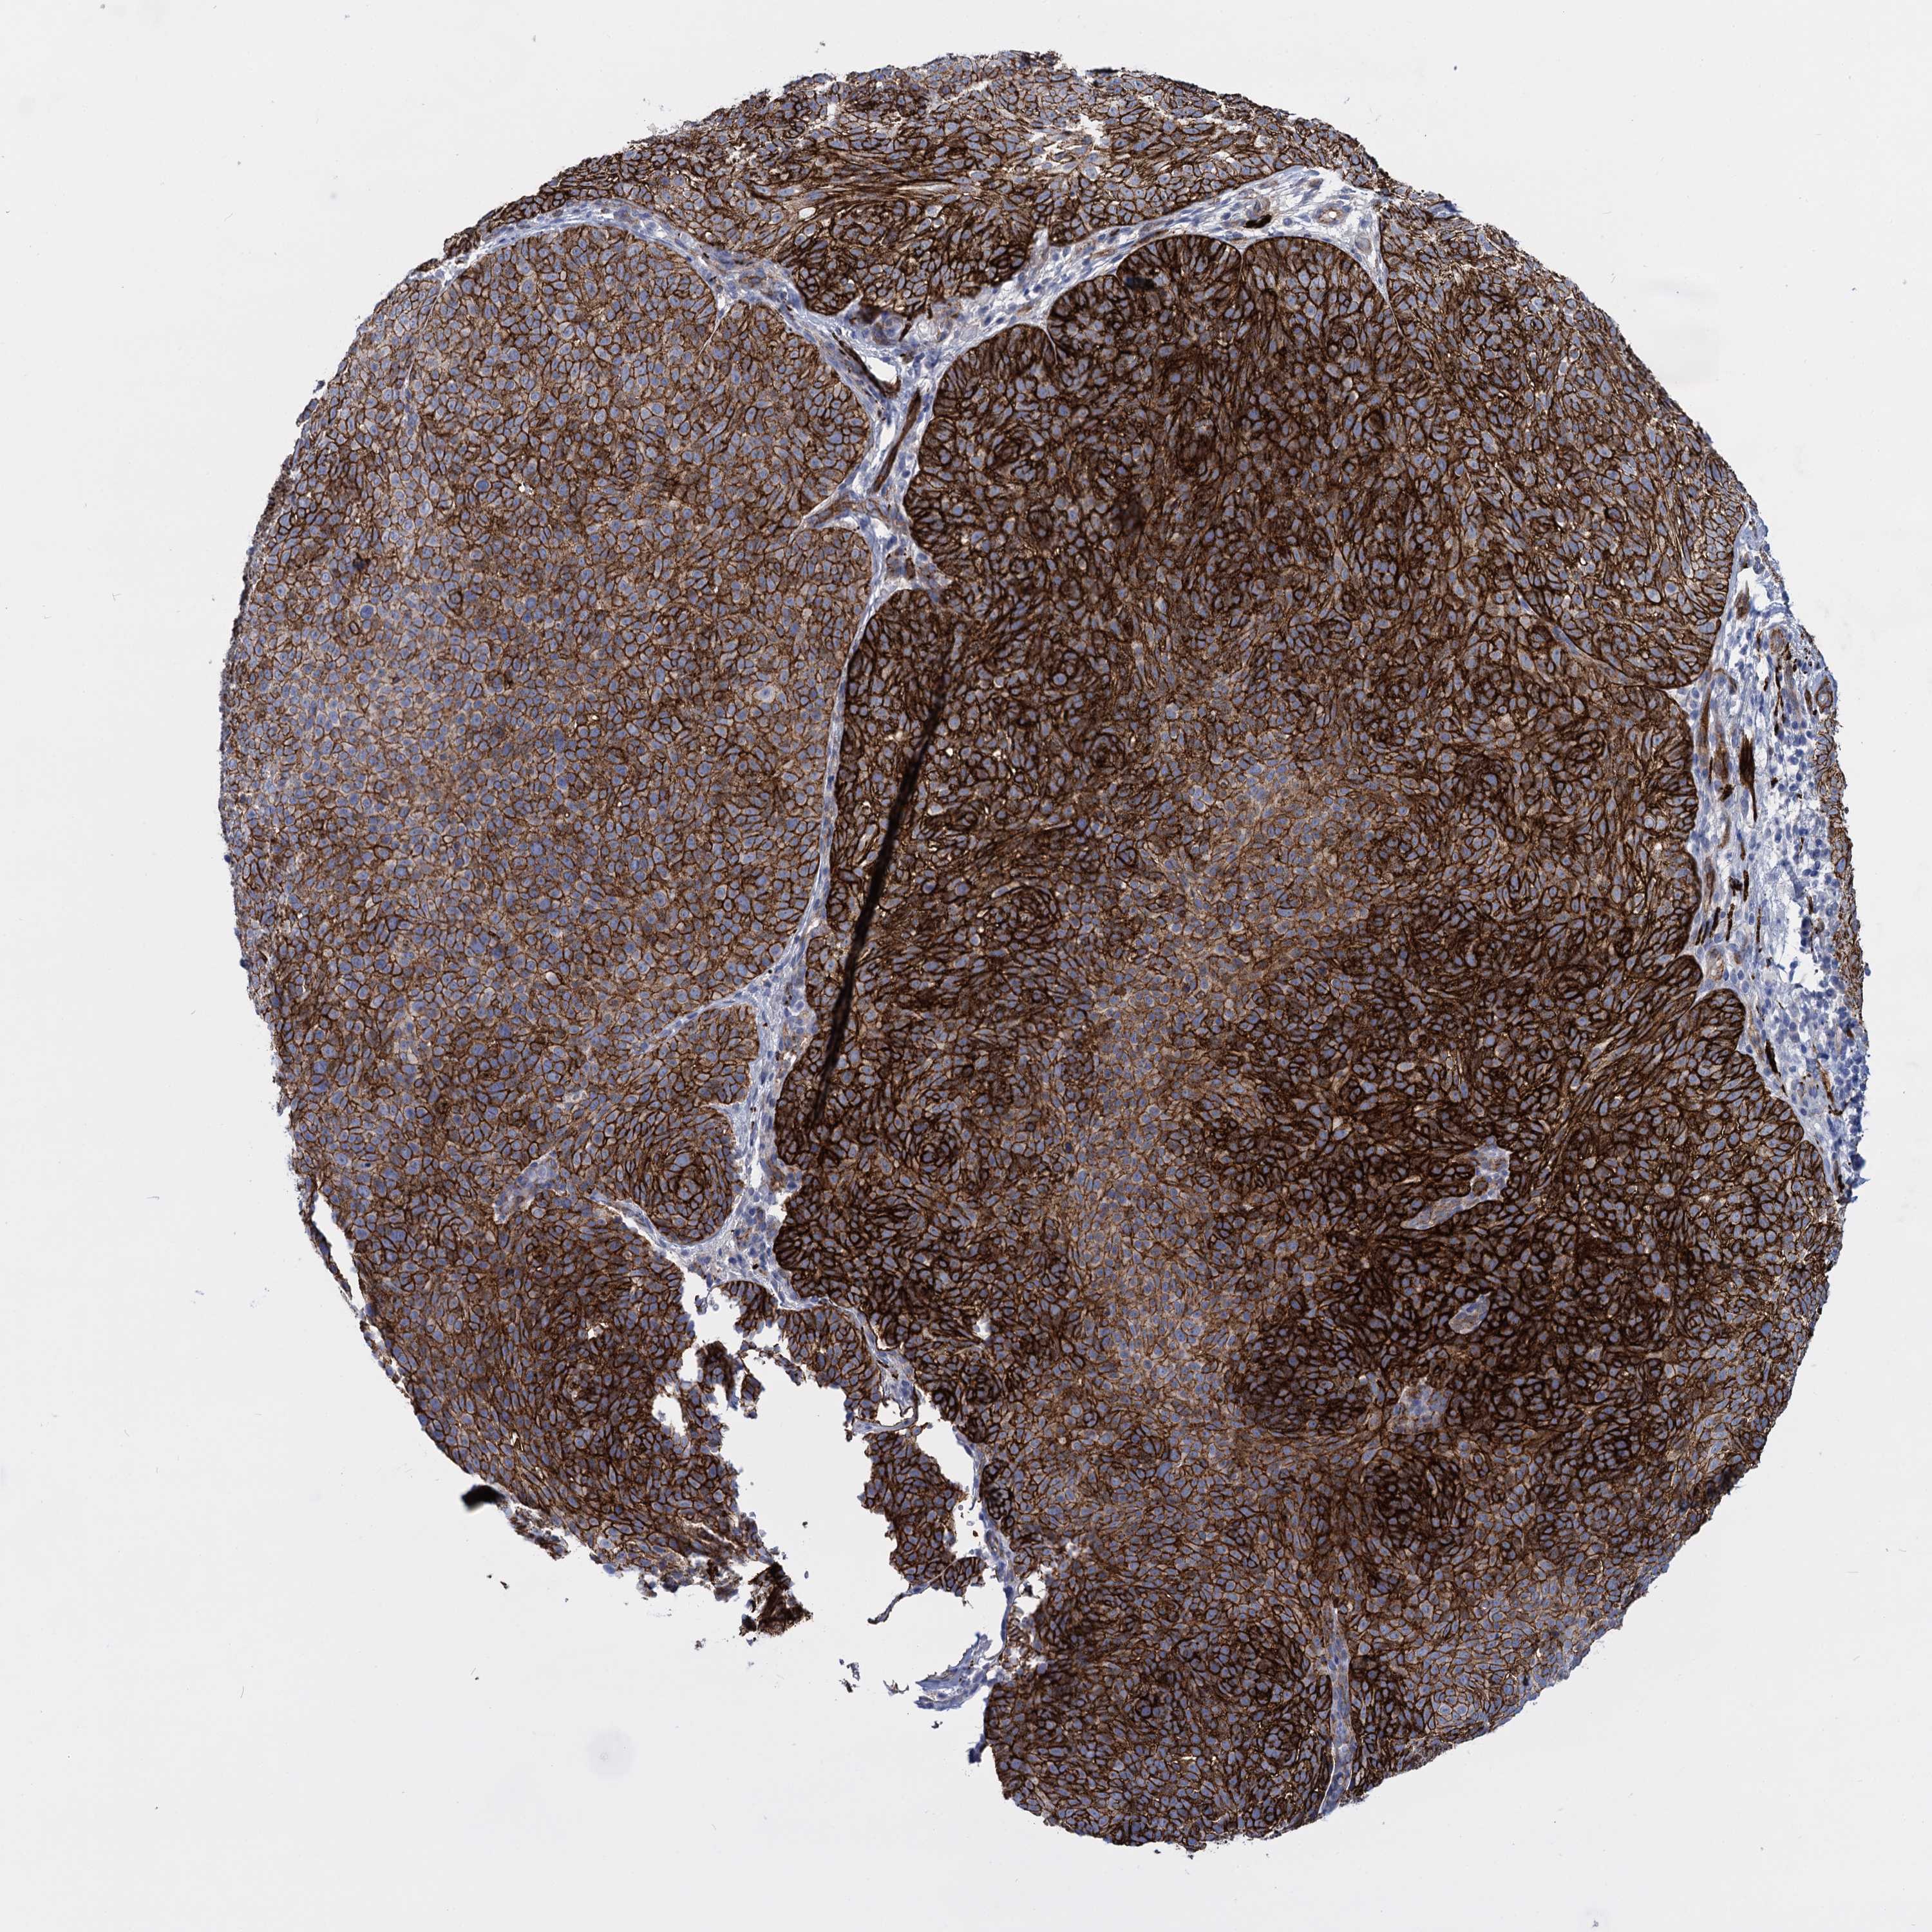

SKIN CANCER - Protein expressioni

A mouse-over function shows sample information and annotation data. Click on an image to view it in a full screen mode. Samples can be filtered based on level of antibody staining by selecting one or several of the following categories: high, medium, low and not detected. The assay and annotation is described here.

Each image is clickable and will lead to virtual microscopy that enables deeper exploration of all samples and also displays staining intensity scores, fraction scores and subcellular localization as well as patient and tissue information for each sample.

Antibody HPA014404

Staining

High

Intensity

Strong

Quantity

>75%

Location

Nuclear

Squamous cell carcinoma, NOS